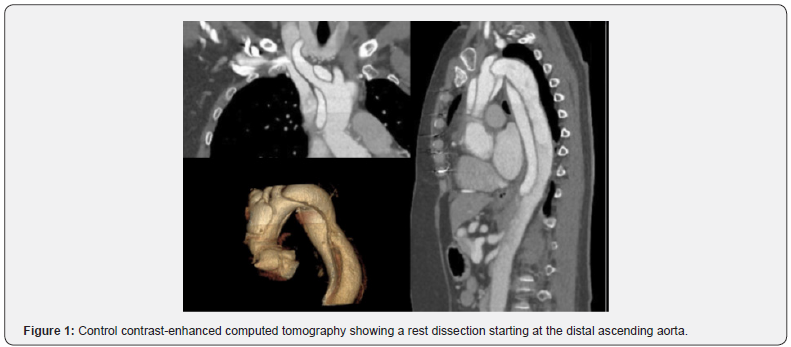

A 59-year-old female patient suffering from recurrent chest pain after acute Stanford Type A aortic dissection (TAAD) presented at our outpatient clinic. Four months prior to this consultation, the patient underwent emergency surgery with aortic root remodeling and replacement of the ascending aorta in deep-hypothermic arrest at another centre. The postoperative period was complicated by pulmonary insufficiency with prolonged ventilation. At the present visit in our department, a control contrast-enhanced computed tomography was performed showing a rest dissection starting at the distal ascending aorta was seen (Figure 1). Additionally a moderate aortic valve regurgitation was seen at transesophageal echocardiography (Figure 2). The patient was urgent taken to the operating theatre for complete open repair. Cardiopulmonary bypass was initiated by re-cannulation of the right axillary artery and the right femoral vein. Hypothermic circulatory arrest at 17.7°C was instituted for implantation of a frozen elephant trunk (E-vita OPEN PLUS Hybrid Stentgraft System 24mm with a stentgraft length of 130mm; Jotec GmbH, Hechingen, Germany), arch replacement and replacement of the aortic valve using a rapid-deployment valve system (23mm) after removing the native aortic valve leaflets. Antegrade brain perfusion was performed for 42 minutes and cross-clamp time was 93 minutes. The postoperative course was uneventful and respirator weaning was achieved within 5 hours. On postoperative day 2, the patient was transferred to the general ward. The patient was discharged home on postoperative day 14 showing excellent aortic valve function, without regurgitation and optimal aortic repair (Figure 3,4). On 6 months follow-up these data could be confirmed (Figure 5).